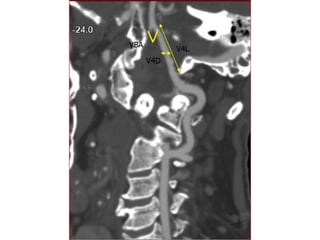

The document discusses the posterior arterial circulation of the brain, including the arteries that supply blood to the brainstem and cerebellum. It outlines the main arteries - the vertebral arteries, basilar artery, posterior inferior cerebellar artery (PICA), and anterior inferior cerebellar artery (AICA) - and describes their segments and typical vascular territories. The document also notes there can be variations in the anatomy of these arteries and lists some references for further information.